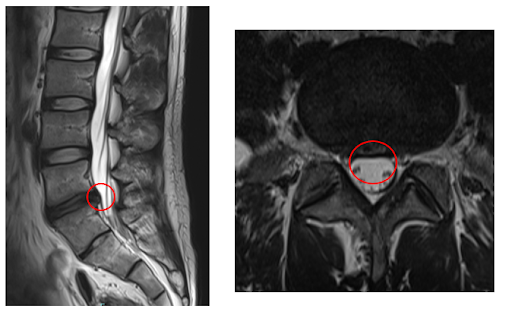

┃検査・診断

赤い枠で示されている部分(L5/S)に、ヘルニアを認めました。